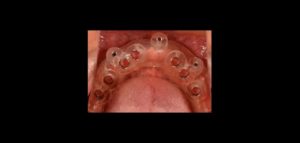

El número de pacientes que requieren prótesis sobre implantes ha aumentado considerablemente en los últimos años. La osteointegración de los implantes dentales es el requisito